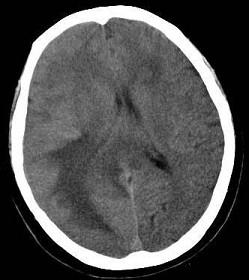

问题 男,62岁,既往有右肺腺癌史,现出现头痛、头晕、恶心、视物模糊,CT检查如图,最可能的诊断是()

选项 A.脑梗死 B.胶质瘤 C.脑膜瘤 D.畸胎瘤 E.脑转移瘤

答案 E